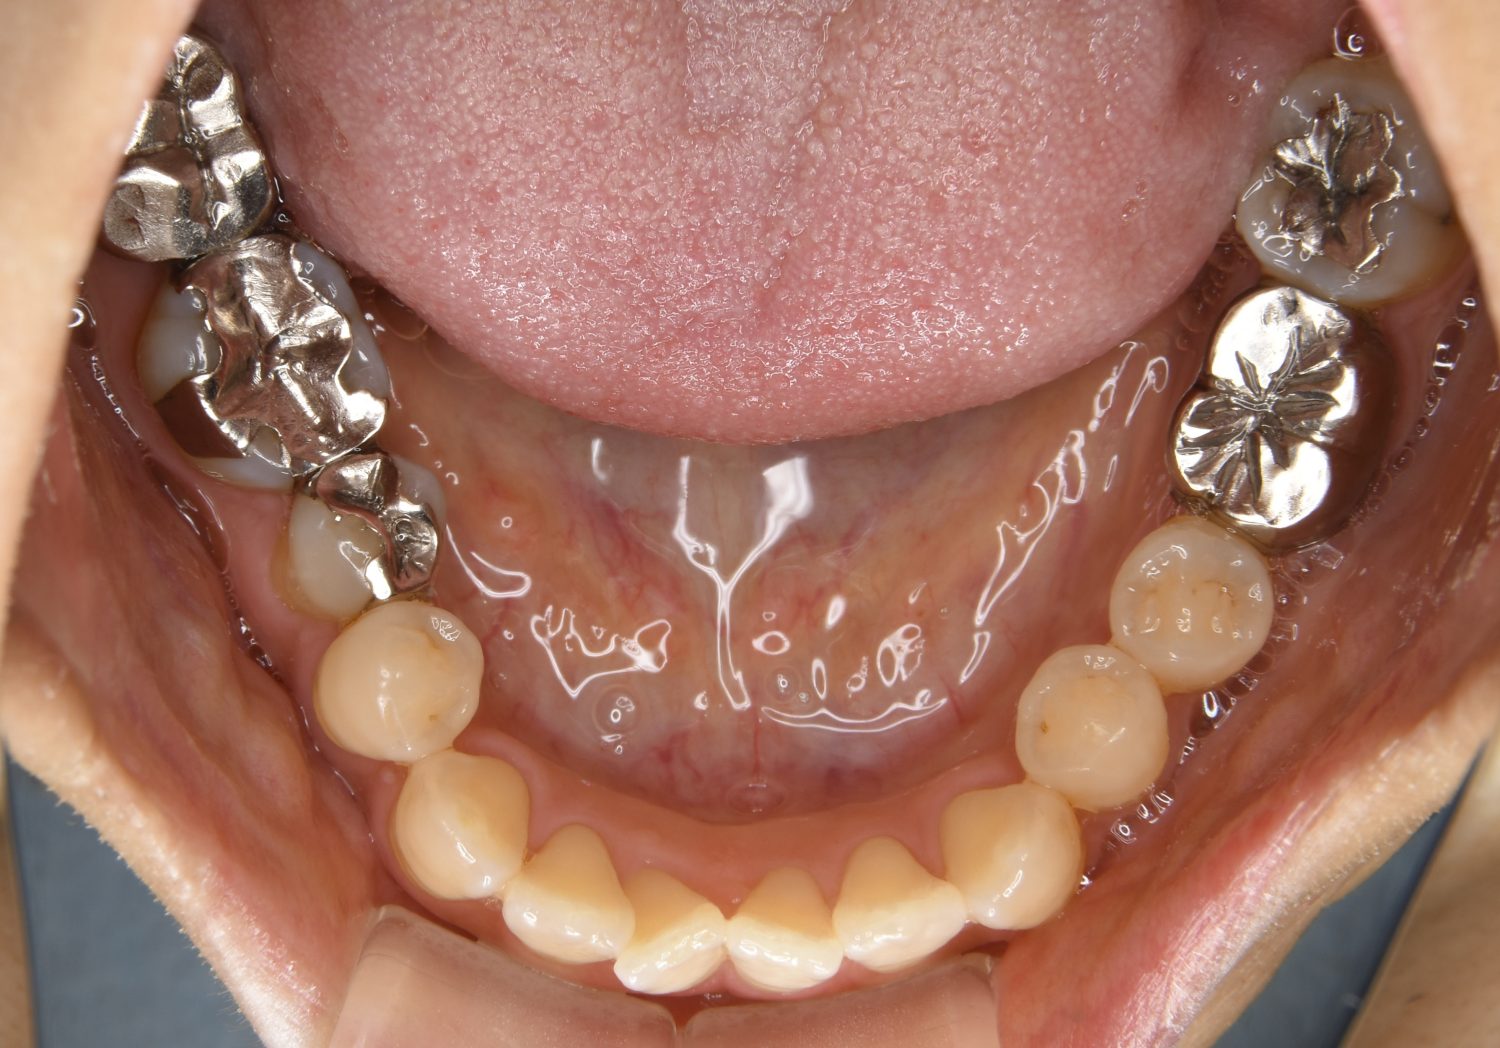

Before

主訴

歯の凸凹を治したい。

治療内容

アライナー(インビザライン)にて非抜歯で治療を行いました。

上下前歯部に叢生(凸凹)が認められる状態でした。歯列の遠心移動を行うことで機能面および審美面が改善されました。